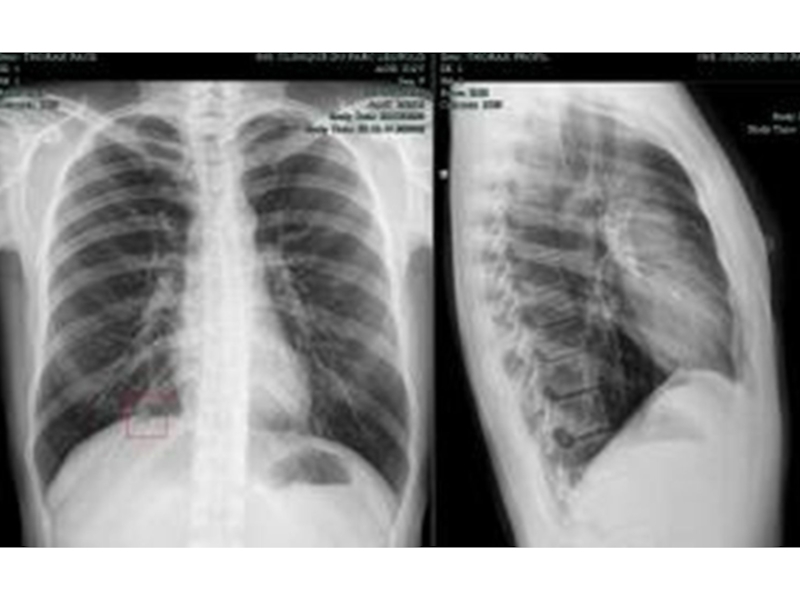

Слайд 38Структуры, различимые на рентгенограмме легких

Легочные поля

Тень средостения

Костные концы ребер

Межреберные промежутки

Ключицы

Корни

легких

Синусы плевры

Структуры, различимые на рентгенограмме легкихЛегочные поляТень средостенияКостные концы реберМежреберные промежуткиКлючицыКорни легкихСинусы плевры

Слайд 39Рентгенограмма легких

Рентгенограмма легких

Слайд 41Боковая проекция

Боковая проекция